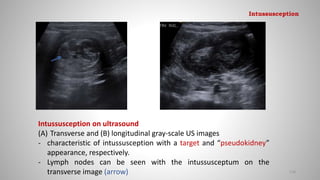

Intussusception on ultrasound

(A) Transverse and (B) longitudinal gray-scale US images

- characteristic of intussusception with a target and “pseudokidney”

appearance, respectively.

- Lymph nodes can be seen with the intussusceptum on the

transverse image (arrow) 128